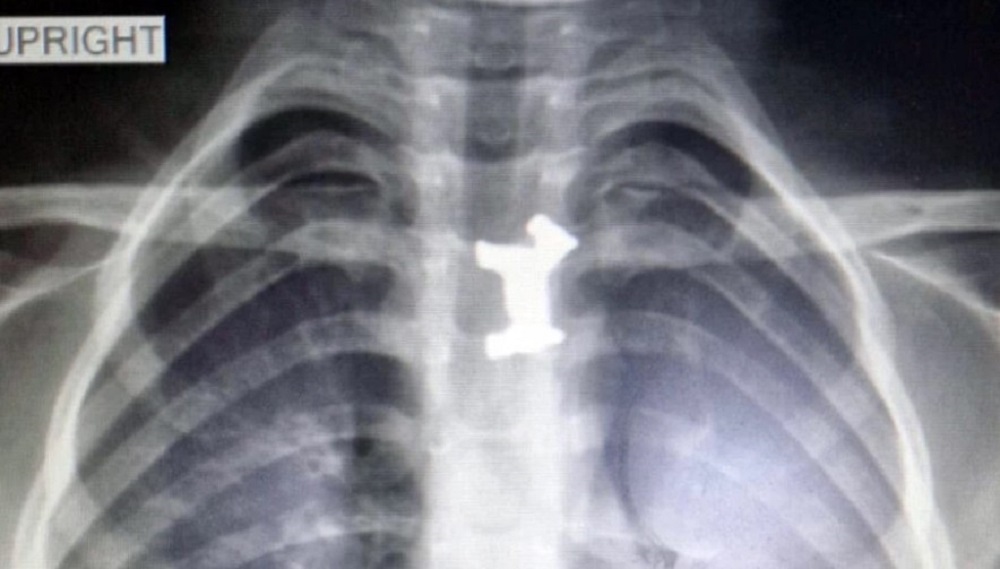

Όπως μεταδίδει η ΕΡΤ, το αγοράκι εμφάνισε σιελόρροια, οι γονείς του το πήγαν στο Γενικό Νοσοκομείο Σερρών όπου εξετάστηκε από τους γιατρούς, η ακτινογραφία έδειξε ότι είχε καταπιεί και είχε σφηνώσει στον οισοφάγο του ένα μεταλλικό παιχνίδι. Αποφασίστηκε η διακομιδή του στο Ιπποκράτειο Νοσοκομείο Θεσσαλονίκης.

Εκεί οι παιδίατροι ακολούθησαν την προβλεπόμενη διαδικασία σε αντίστοιχες περιπτώσεις, το πρωί υποβλήθηκε σε χειρουργική επέμβαση και οι γιατροί κατάφεραν να αφαιρέσουν με επιτυχία το μεταλλικό σκυλάκι από τον οισοφάγο του παιδιού. Ο μικρός νοσηλεύεται προληπτικά και είναι καλά στην υγεία του. Το σκυλάκι προερχόταν από γνωστό επιτραπέζιο παιχνίδι.